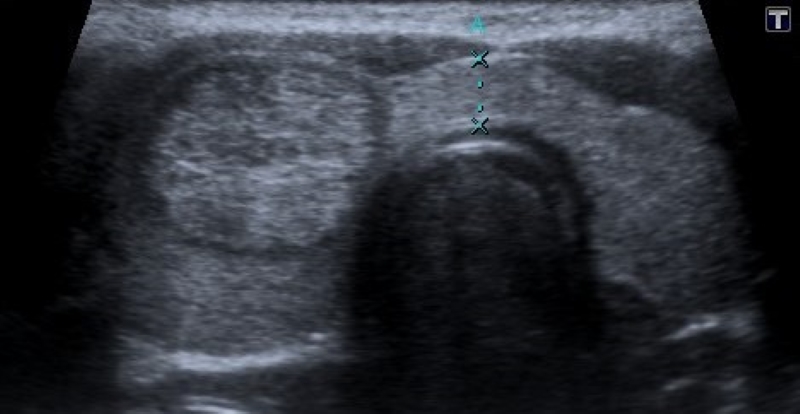

Calcificaciones

Focos ecogénicos que pueden clasificarse según su tamaño en microcalcificaciones (Fig. 15) y macrocalcificaciones (Fig. 16). Las primeras miden menos de 1 mm y no presentan sombra acústica posterior, a diferencia de las macrocalcificaciones que son mayores de 1 mm con sombra acústica posterior.

Las microcalcificaciones presentan un alto riesgo de malignidad. De hecho, algunos autores las consideran por sí solas un predictor de malignidad20, y otros sostienen que la presencia de microcalcificaciones sumado al aumento de la vascularización central y una imagen ganglionar patológica son suficientes para indicar una punción aspiración con aguja fina23.

El artefacto en cola de cometa (Fig. 17) es producido por la reverberación en los quistes coloides, que pueden confundir con microcalcificaciones. A diferencia de estas últimas, el artefacto en cola de cometa se visualiza como una línea ecogénica brillante con un triángulo o líneas ecogénicas posteriores, y se suele asociar a benignidad2.